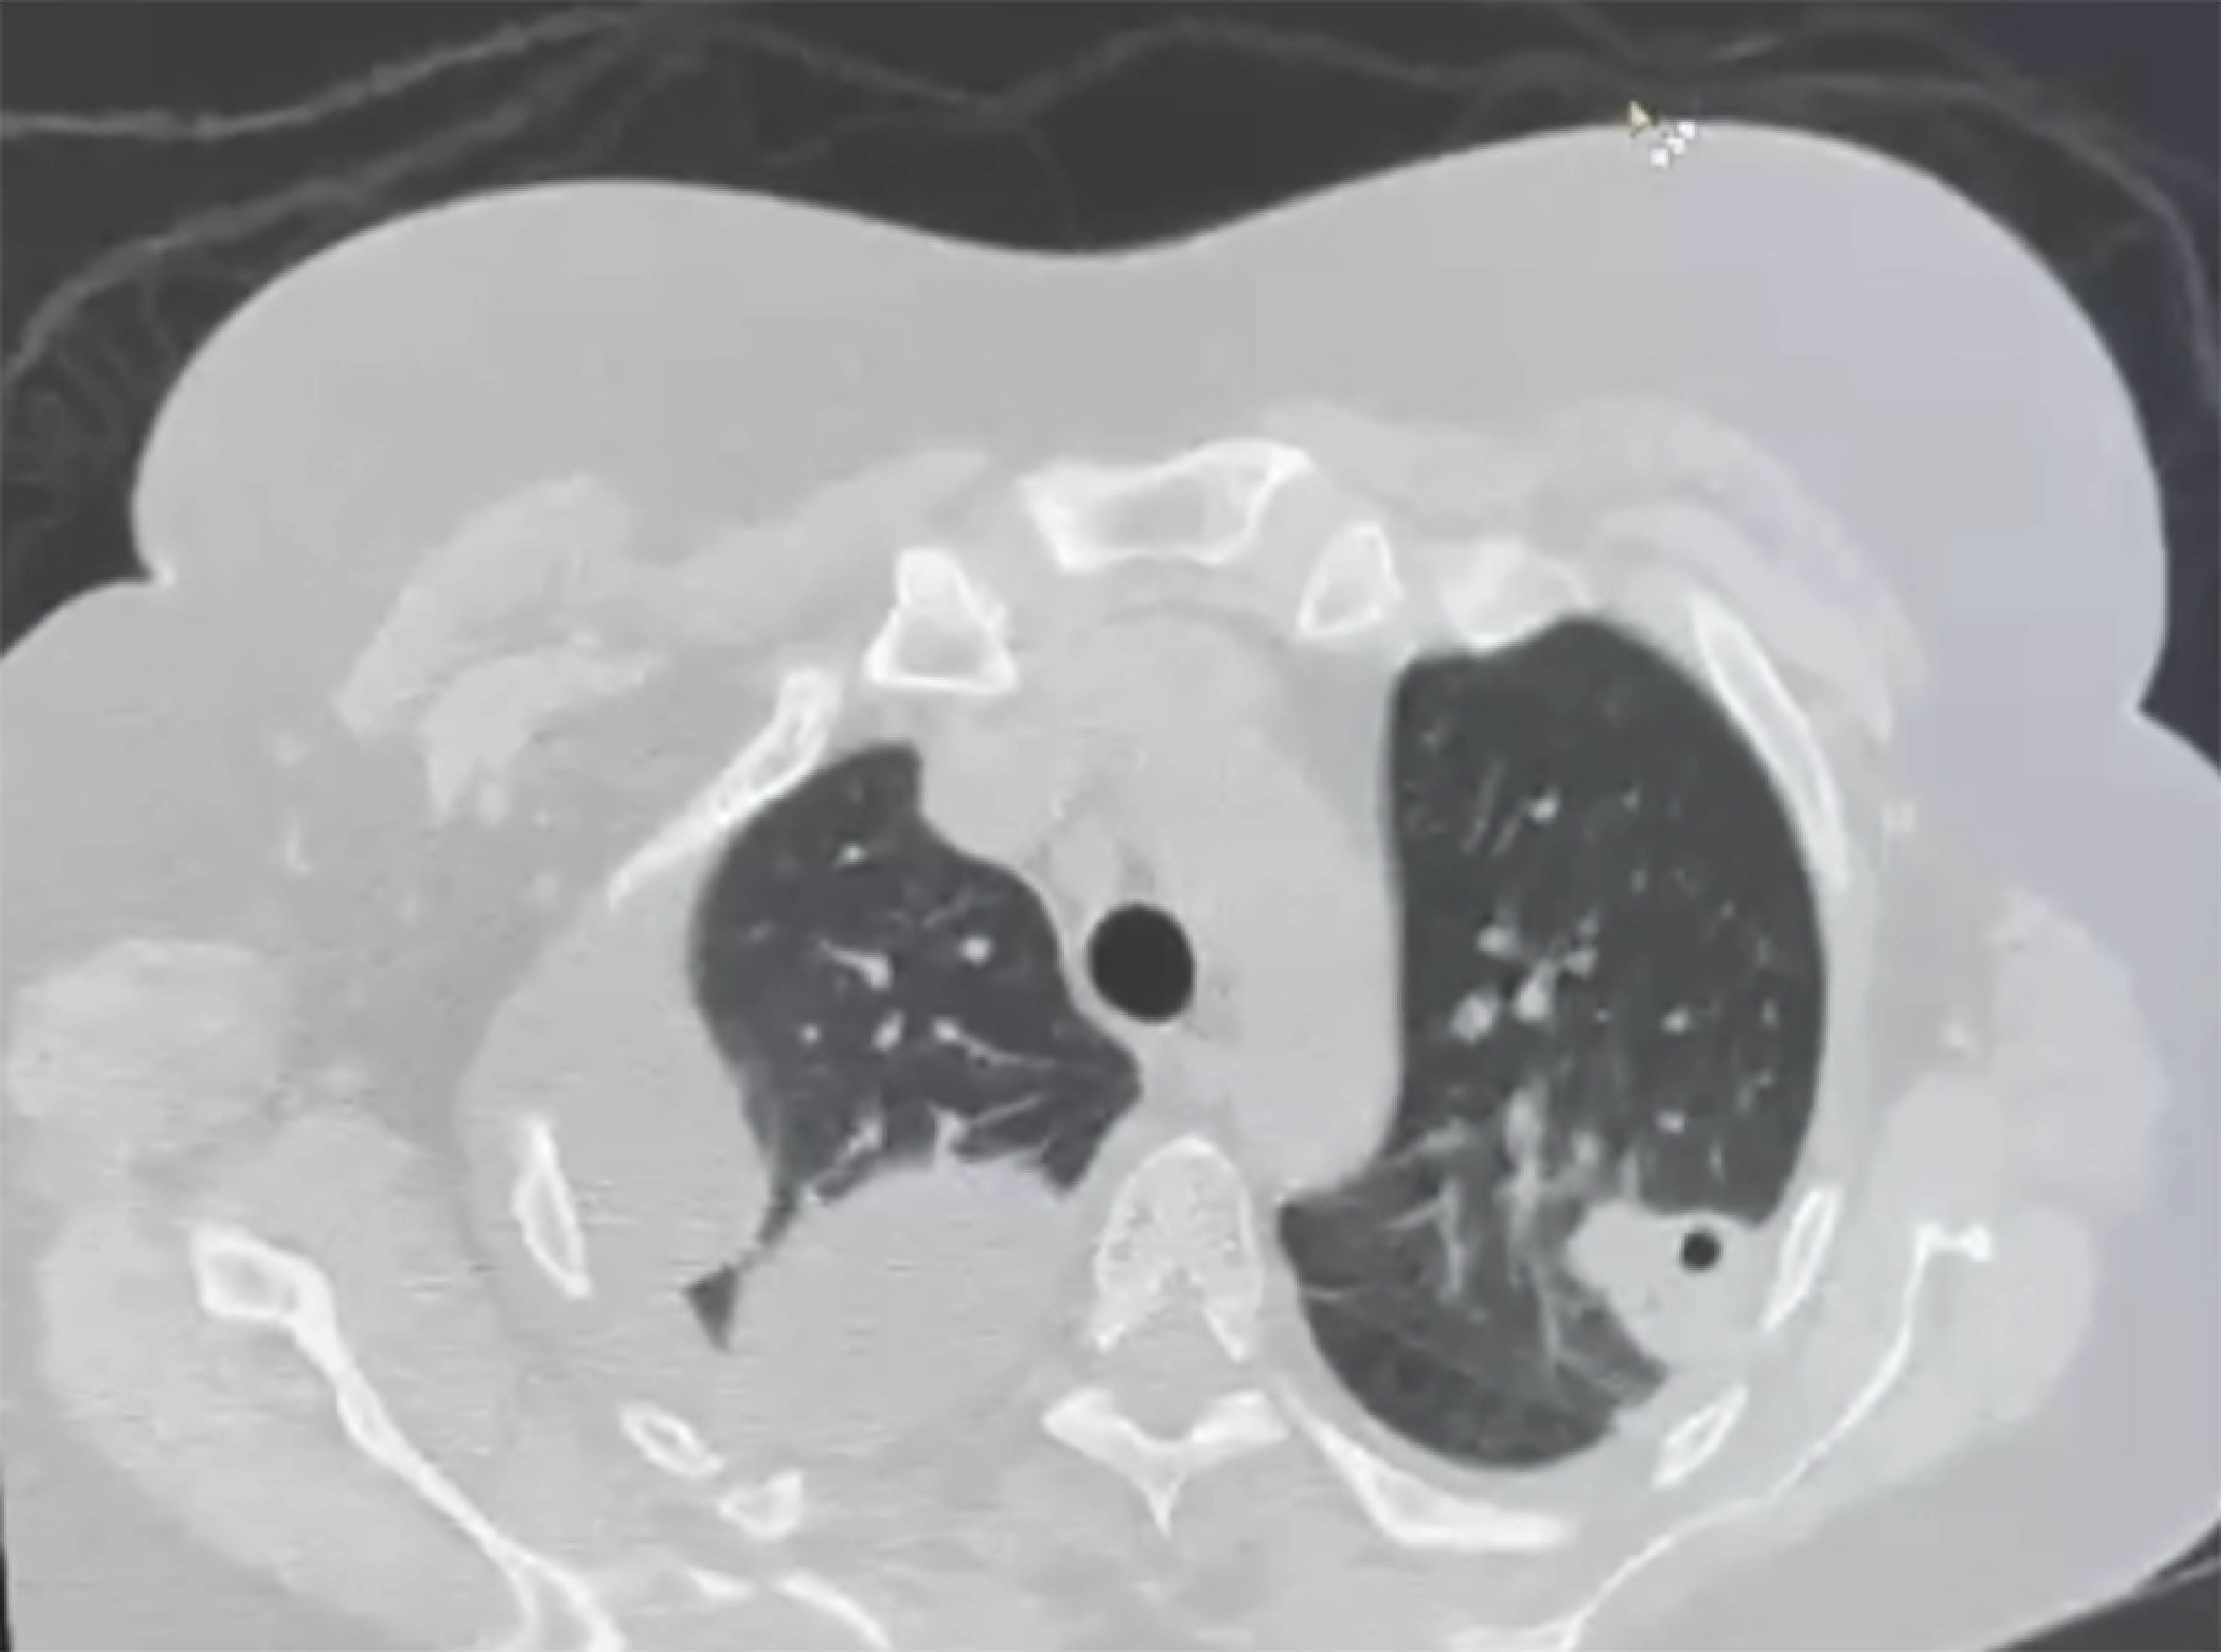

La TAC de tórax demostró nódulos pulmonares bilaterales, en el hemitórax derecho se observa empiema multiloculado y en el hemitórax izquierdo un nódulo cavitado que alude a un proceso infeccioso (Figura 3).